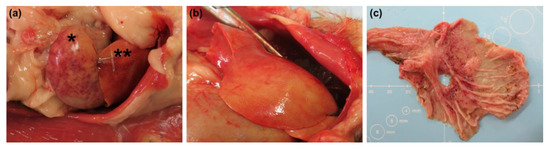

2.3. Tissue Viral Load, Gross Pathology, and Histopathology